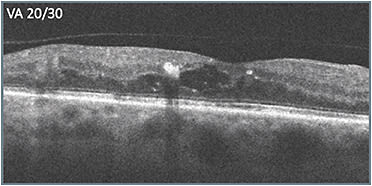

A 54-year-old female presented after having been treated by another physician with approximately 8 treatments for nonproliferative diabetic retinopathy (NPDR) and reduced vision (20/40). Leakage was present on the previously obtained initial ultra-widefield angiography. The previously obtained initial OCT scans (A) showed cystic fluid but intact retinal layer integrity, with the exception of some attenuation of the outer retinal layers, and only 1 noticeable hyperreflective focus nasally. Edema persisted and therapy was switched. After 2 treatments with the second therapy, vision improved slightly to 20/30 and edema improved (B).

Unfortunately, the patient was unable to return for 10 weeks. When she did return, (C) her vision had worsened dramatically (20/150). In deciding what to do, the apparent progression of disease signs that had occurred over time (B & C) were considered. Retinal layer disorganization progressed, including what appeared to be signs of DRIL. More hyperreflective foci appeared as well, presumably indicating accumulation of exudate, including near the fovea. The decision was made to switch to a different class of therapy, which produced a favorable response (D). Vision improved from 20/150 to 20/60, and the retinal anatomy appeared as intact as it had been during the course of treatment.